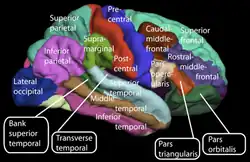

The cerebral cortex is generally classified into four lobes: the frontal, parietal, occipital and temporal lobes. The lobes are classified based on their overlying neurocranial bones.[4] A smaller lobe is the insular lobe, a part of the cerebral cortex folded deep within the lateral sulcus that separates the temporal lobe from the parietal and frontal lobes, is located within each hemisphere of the mammalian brain.

Upper motor neurons in the primary motor cortex which is located in the frontal lobe, send their axons to the brainstem and spinal cord to synapse on the lower motor neurons, which innervate the muscles.[9][10] Through this connection signals from the Cerebrum control voluntary movements of the body.[10] Damage to upper motor neurons can lead to lesions called upper motor neuron lesions. These lesions result in muscle weakness, spasticity, hyperreflexia, and Babinski sign.[11]

- Visual – The main visual area (V1) in the occipital lobe notices edges, colors, and movement. Nearby areas (V2–V5) help the brain recognize objects and faces.[14]

- Auditory – The main hearing area in the upper temporal lobe senses the pitch and loudness of sounds. Nearby areas then help the brain process more complex sounds like speech and music.[15]

- Somatosensory The main touch area in the parietal lobe maps feelings like touch, pain, temperature, and body position. Each body part has a matching area in the brain, and nearby regions help with spatial awareness and using objects.[16]

Speech and language are mainly attributed to parts of the cerebral cortex. Motor portions of language are attributed to Broca's area within the frontal lobe. Speech comprehension is attributed to Wernicke's area, at the temporal-parietal lobe junction. These two regions are interconnected by a large white matter tract, the arcuate fasciculus. Damage to the Broca's area results in expressive aphasia (non-fluent aphasia) while damage to Wernicke's area results in receptive aphasia (also called fluent aphasia).